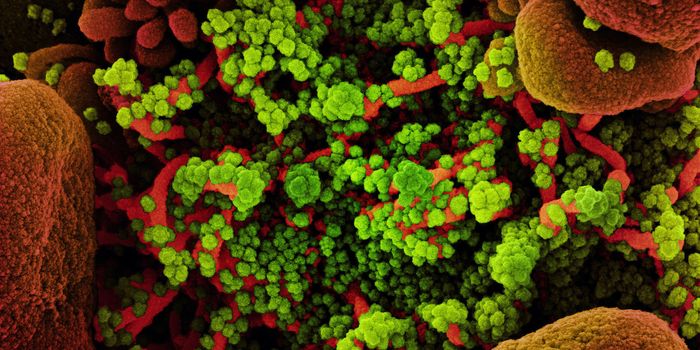

MAY 10, 2021MicrobiologyThe pandemic virus SARS-CoV-2 has changed the world in devastating ways, taking hundreds of thousands of lives & new var ...